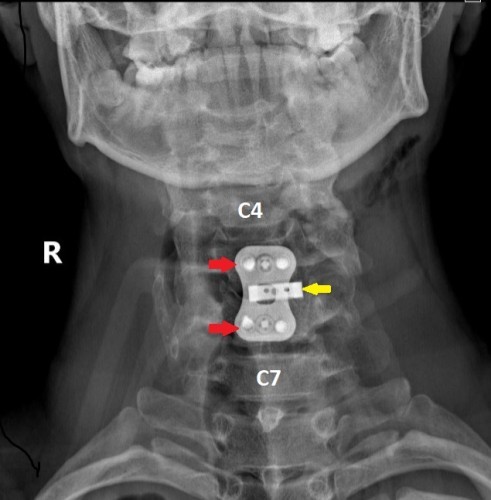

Операцию проводили хирурги Петр Галкин и Михаил Ветров. Под увеличением, с использованием операционного микроскопа, через небольшой разрез кожи по передне-боковой поверхности шеи была удалена травматическая грыжа диска. Затем под рентген-контролем был успешно вправлен вывих, а позвонки зафиксированы при помощи титановой пластины и пластикового кейджа между позвонками.

На следующий день после операции пациенту уже разрешили вставить и ходить в жестко фиксирующем шею воротнике. Контрольное обследование на третий день показало, что все функции организма удалось сохранить, имплант надежно фиксирован, а шов отлично затягивается, рассказал заведующий нейрохирургическим отделением Владимир Сериков. Пациента выписали на 5-й день после операции.